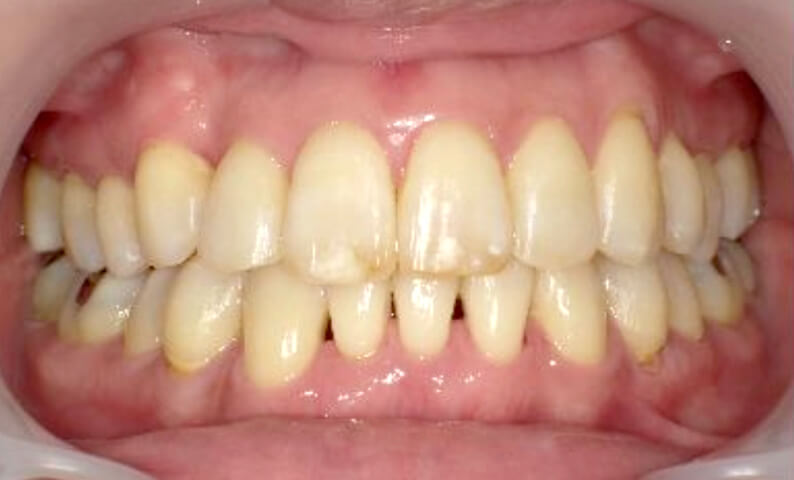

症例_002 下顎だけの部分矯正

治療期間:6ヶ月金額:21万円+税女性前歯のデコボコ下の前歯だけ

| Before | After |